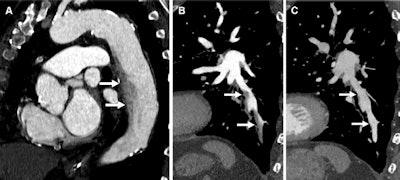

Flow artifact from slow blood flow along the inner curves of arteries in two patients. (A) Sagittal oblique MPR from a CT examination timed off the aorta in a 78-year-old man with chest pain shows smokelike nonuniform opacification along the inner curve of the descending aorta (arrows), a common location for flow artifacts on CT images. (B, C) Sagittal oblique MPR (B) of the left-sided pulmonary arterial tree in a 76-year-old man with chest pain shows smokelike nonuniform opacification along the inner curve of the posterior basal segment left lower lobe arteries (arrows in B). These findings resolved (arrows in C) on a subsequent CT image (C) with a 70-second delay. Image and caption courtesy of the RSNA.